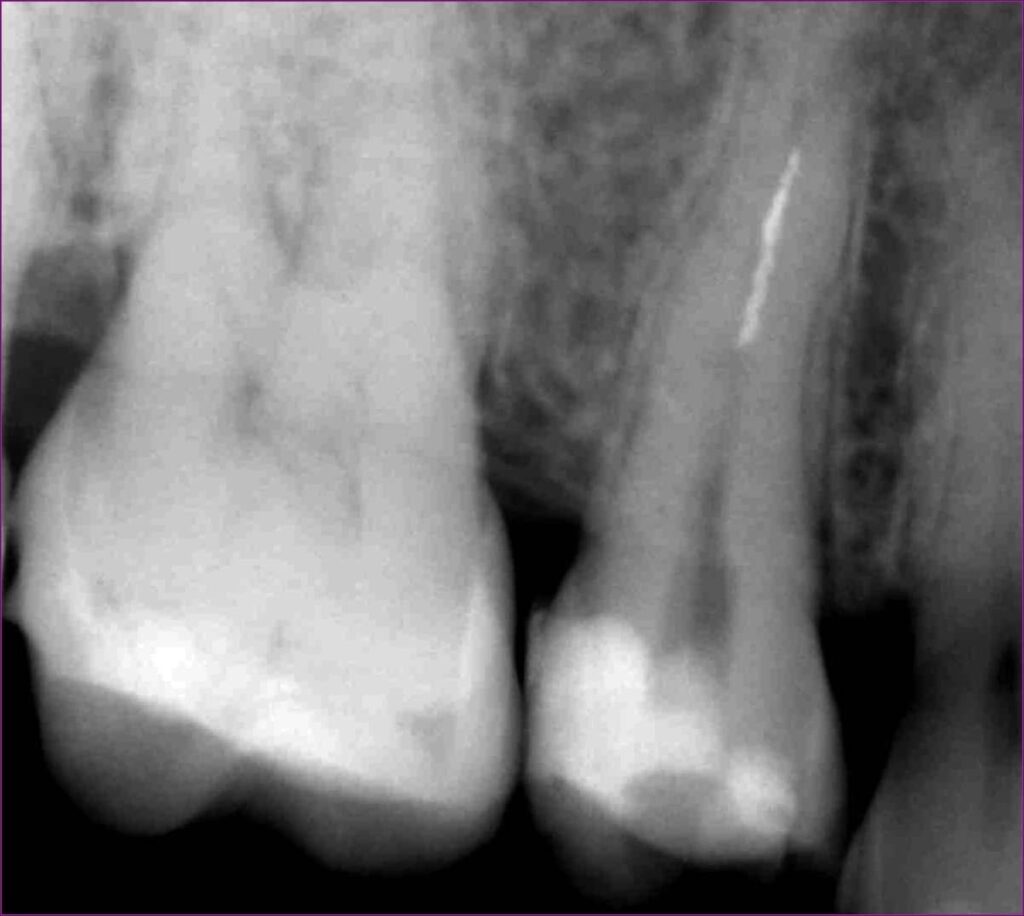

A fogakat szemből érő ütések jelei jól megfigyelhetőek a frontfogakon: a jobb felső nagymetsző koronai részéből egy nagyobb darab letört. Ráadásul az egyik alsó metszőfog több árnyalattal sötétebb, mint a többi, ugyanis elhalt. Utóbbira egyértelmű bizonyíték, hogy a röntgenfelvételen a bal alsó középső metszőfog gyökércsúcsa körül sötét folt látható, ami gyulladásra utal.

Első lépésként a gyulladás megszüntetésére mikroszkópos gyökérkezelésre került sor. A sikeres gyökérkezelést jelzi, hogy a második röntgenen láthatóan a gyulladás meggyógyult, a sötét folt eltűnt.